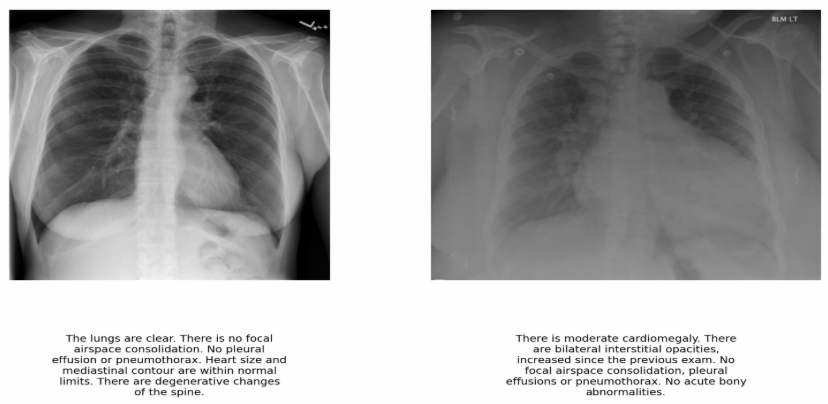

We have used the IU-Xray [11] dataset which is a publicly available collection of radiographic images paired with their corresponding radiology reports. This dataset is widely used for research in medical imaging. The dataset comprises a total of 5,910 chest X-ray images along with their associated findings in the form of radiology reports. Each image in the dataset is accompanied by a detailed textual description that provides diagnostic insights. Fig. 2 shows two sample X-ray images with associated reports.

Refer to caption

Figure 2: Sample X-ray images and corresponding findings in the form of reports from the IU-Xray dataset. These reports are treated as the ground truth.